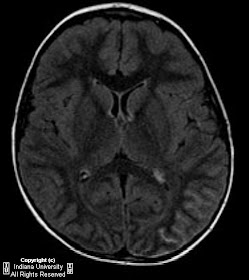

Findings

Hyper density on CT in the left tempero-occipital region which may represent calcium and/or hemorrhage, possibly parenchymal and in the subarachnoid space. Non contrast MRI demonstrates FLAIR hyper intensity in the left tempero-occipital region involving cortex and subarachnoid space. Absent mass effect and vasogenic edema. On contrast enhanced MRI, there is enhancement within sulci in this region and mild asymmetric enlargement of the left choroid plexus.

Radiology

Calcification may be seen on plain film of the skull, and on the CT scanogram. Significant calcium deposition before the age of 2 is uncommon. Tram-tracking is the characteristic finding, resulting from calcification of apposing gyri surrounding a dilated sulcus. CT demonstrates gyriform, curvilinear calcification, most prominent in the parietal and occipital lobes ipsilateral to the facial nevus. Secondary changes in the skull are sometimes present, such as enlargement of the paranasal sinuses and mastoid air cells. Strong post-contrast enhancement may be seen in both the angiomata, as well as the ipsilateral choroid plexus. Prominent collateral drainage through subependymal and medullary veins may be seen, particularly with angiography or MR venography.